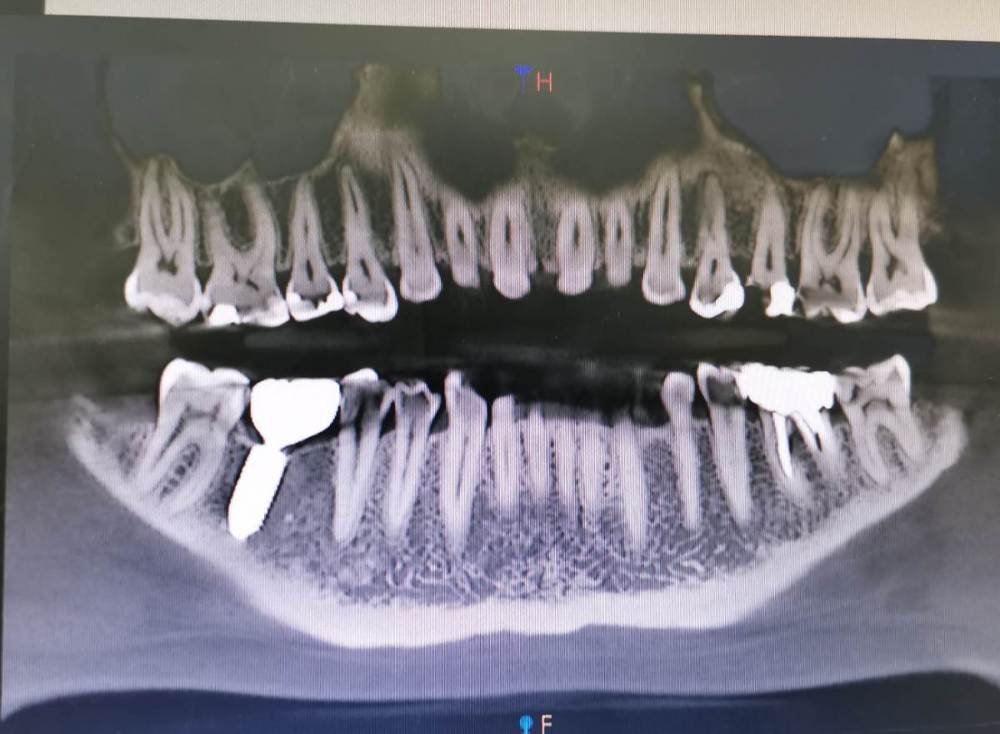

У меня немного кривые и съехавшие после удаления одной 6 и всех 8 зубы. Из-за этого зубы начали скалываться и портиться, начал щёлкать сустав с правой стороны (особенной после постановки коронки на 6 зуб снизу слева)

В это же время мне поставили диагноз пародонтит, нашли карманы где-то глубокие, где-то нет. Я это пролечила - делали закрытый кюретаж, чистку поддесневых и над десневых отложений. Теперь мне кажется, что некоторые зубы качаются - если руками пошатать, то чувствуется какой-то треск (верхние левые 3,4,6,7).

Подскажите можно ли мне при таком состоянии пародонта и очень тонкой десне ставить брекеты? Мне 35 лет.

Снимок сделан до кюретажа.